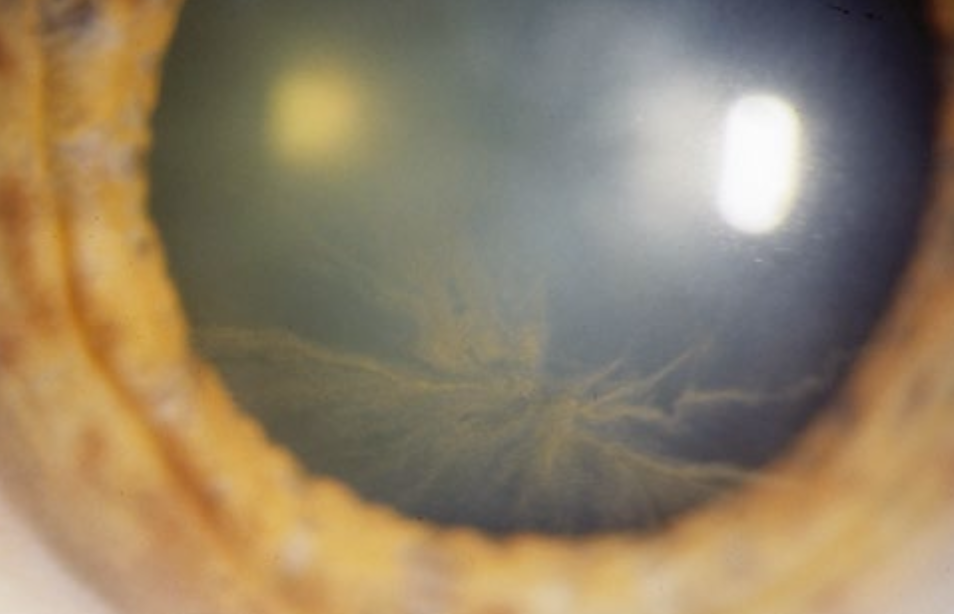

Vortical keratopathy is a condition where the corneal epithelium develops pigmented or deposit lines in a swirl (vortex) pattern. Which conditions can cause vortical (swirl) pigmented deposits in the cornea?

Metabolic diseases: Fabry’s disease

Medications: Amiodarone

Which viruses can cause dendriform corneal lesions, and what is their pattern?

Neurotropic viruses - Herpes Simplex Virus (HSV)

form a branching (tree-like) pattern, visible with staining

branching b/c corneal nerves themselves have a branching innervation